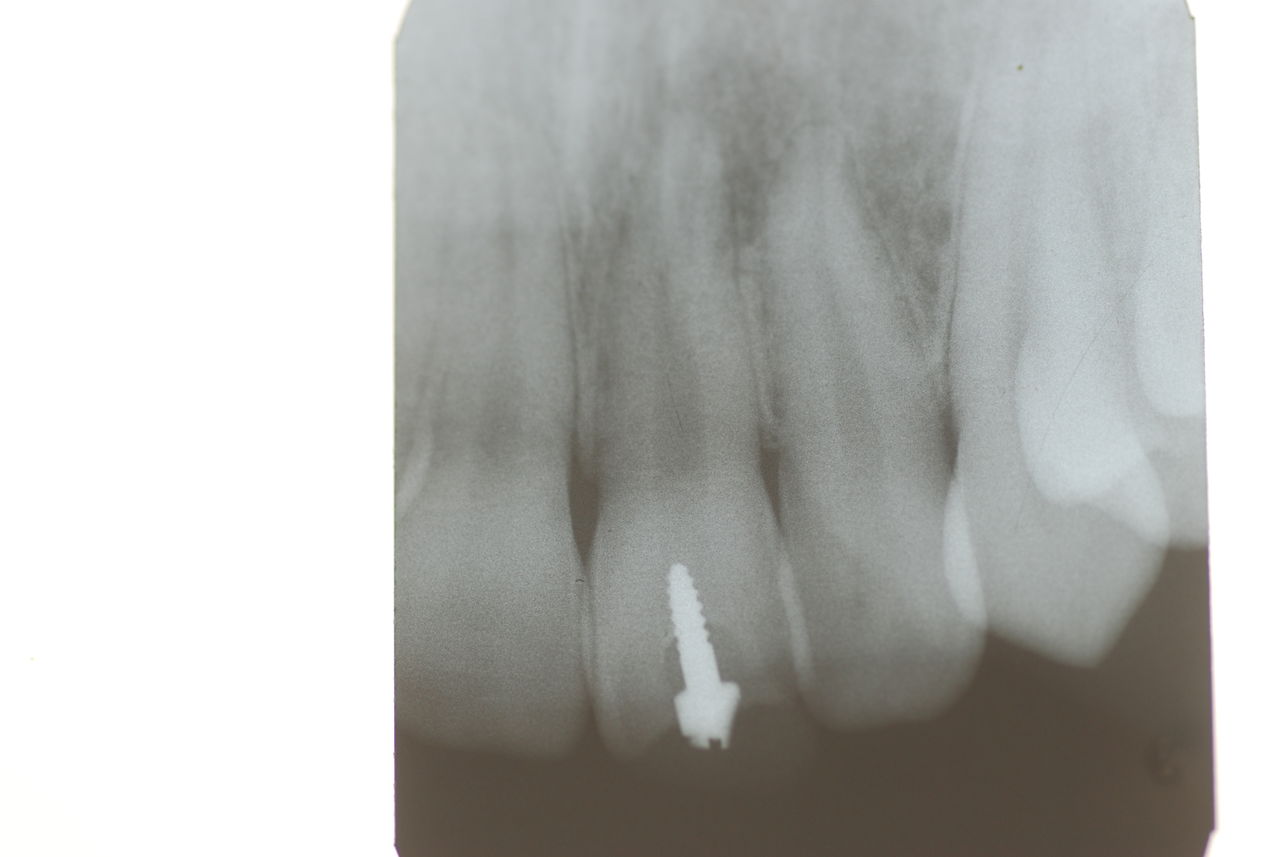

1、先ず一番目は、10才、右の前歯が反対咬合と言って上の歯と下の歯が逆の位置にあり、他の部分があまり咬合していない10才の子供の例でした。噛むと痛みが突然出てしばらく続いていたという症例。

診断を咬合性(歯と歯の噛みあわせ)の急性歯髄炎(神経の炎症)と判断したが、では治療はどうすればいいのかという相談。

レントゲンと話の内容から、食いしばりや歯ぎしりによるものではなく、単純にぶつかる歯が少ないので、その時に前歯のところで何か硬い物などを噛んだために外傷性の痛みが来たのではないかという判断でした。炎症でもないので、奥歯にマウスピースなどを入れて前歯を当たらなくした後に、症状が緩解したら、反対咬合という上下の前歯の関係を簡単な小矯正で変更した方がいいという診断と治療方針の提案で解決しました。